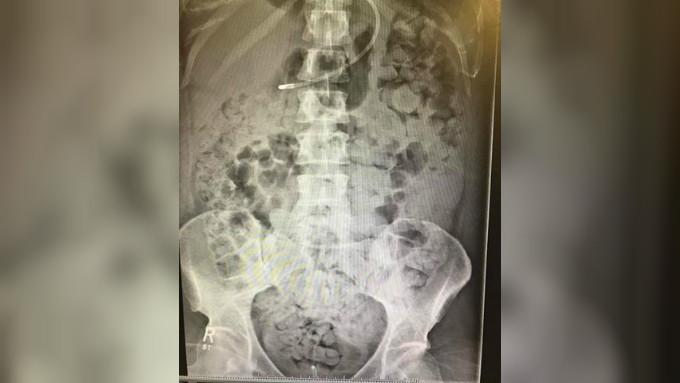

Dari pemeriksaan sinar X yang baru saja diambil, organ dalam tubuhnya hampir tidak terlihat. Ini karena kotorannya telah menyebar di tubuh Kelly.

Rongga dada Kelly penuh dengan tinja, yang membuatnya sulit bernapas, dilansir dari International Business Times, Selasa (28/11/2017).